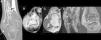

Plain radiography, computerised tomography (CT) and magnetic resonance (MR) were performed (Fig.1), which showed extensive irregular calcification of the interosseous membrane of the leg and several lobulated masses of soft tissues with different levels of mineralisation in ankle and foot. SOC, multiple osteochondromas, chondrosarcoma and disease from microcrystal deposits were included in the differential diagnosis. A biopsy of the soft tissue mass of the lateral face of the ankle was performed and the anatomopathological report was: extra-articular post-traumatic SOC.

Extensive extra-articular SOC. A) CT with no contrast agent in coronal plane which shows extensive irregular calcification of the interosseous membrane (black arrow) and mass of soft tissues in the lateral side of the ankle with scarce mineralisation (White arrow). B) CT with no contrast agent in axial plane which shows masses of soft tissues in the dorsal and lateral side of the ankle, with incipient diffuse mineralisation (arrows). C) MR with axial sequence T1 with no contrast agent, which shows the same masses as in B (arrows), isointense with respect to the muscle. D) MR with axial DP Fat Sat pulse sequence, which shows a mass of adjacent soft tissues to the base of the fifth metatarsal, of intermediate signal intensity due to incipient diffuse mineralisation (arrow). E) MR with coronal 2 GRE sequence which shows the mass of soft tissues on the lateral side of the ankle extending towards the sinus tarsi (arrow).